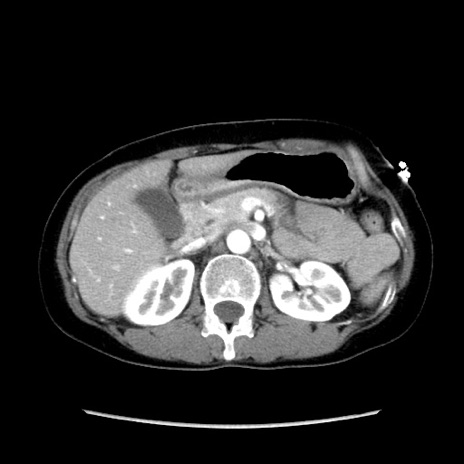

症例32(横断像)

【症例】40歳代 女性

【主訴】上腹部痛、嘔気・嘔吐

【現病歴】約9時間前頃から急に上腹部痛、嘔気、嘔吐が出現。改善しないため救急要請。

【既往歴】子宮頚癌(広汎子宮全摘術、放射線療法)、腸閉塞

【身体所見】腹部:平坦、軟、腸雑音亢進、上腹部を中心に腹部全体に圧痛あり。

【データ】WBC 8400、CRP 0.03